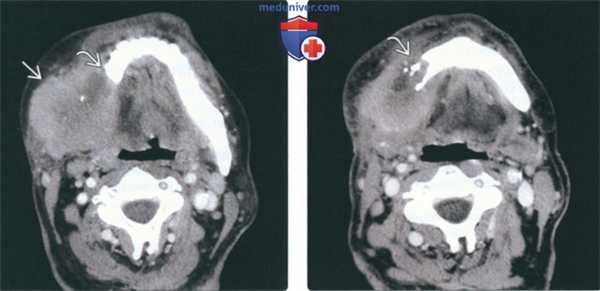

(Слева) На аксиальной КТ с КУ в жевательном пространстве справа визуализируется злокачественная фиброзная гистиоцитома нижней челюсти в виде минимально контрастирующегося солидного объемного образования, разрушающего ветвь и тело нижней челюсти. Жевательное пространство является известным местом возникновения сарком глубоких областей ли ца.

(Справа) На аксиальной КТ с КУ у этого же пациента визуализируется опухоль в жевательном пространстве справа, приводящая к обширной деструкции нижней челюсти. Обратите внимание на асимметрию лица на стороне поражения.

2. КТ при саркоме жевательного пространства:

• КТ с КУ:

о Вариабельная картина контрастирования:

- Обычно неоднородное

• КТ в костном окне:

о Инвазивная опухоль в ЖП с деструкцией нижней челюсти, скуловой дуги или крыловидной пластинки